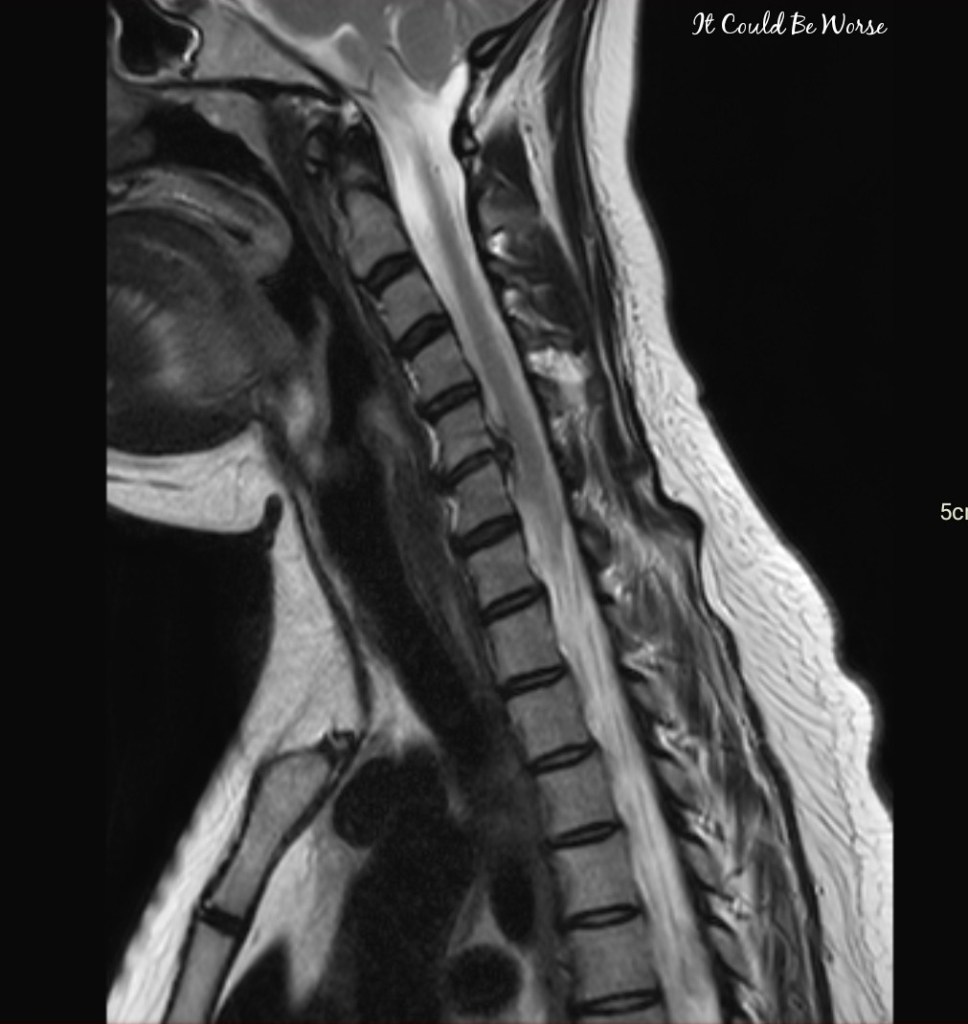

So, I drove back to the VA, and got a CT scan of my neck and spine. I had assumed I would have to wait until the next day to get my report back considering it was late afternoon, but within the hour, my primary care doctor was calling me back and telling me good news, nothing was broken! But bad news, it looks like I have a herniated disc on my C3/C4 spine – which was never there before or after surgery, or in any of the other CT scans I’ve had done – and you know I’ve had plenty. (See image below. This is an older CT scan I had before my ACDF surgery; you can see there is no herniated disc at C-3/C-4.)